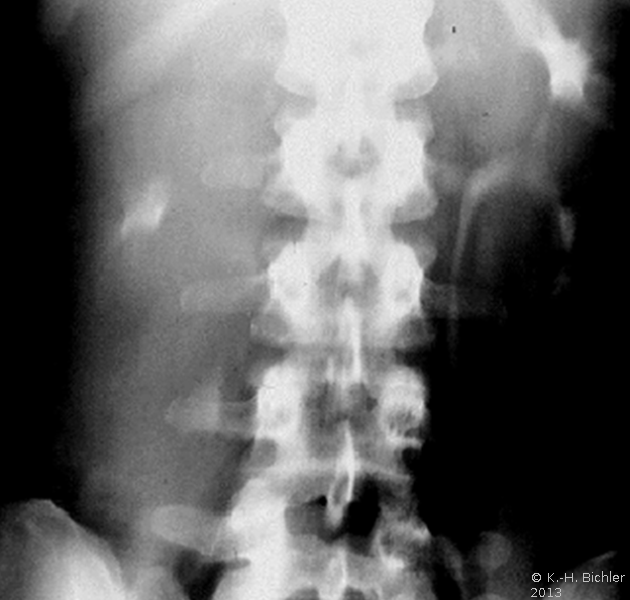

Von Wichtigkeit sind die bildgebenden Verfahren: Sonographie, CT bzw. AUR.

Beispielhaft die Darstellung eines ausgedehnten Nierenabszesses in Sonographie, CT und AUR (Abbildung 6).